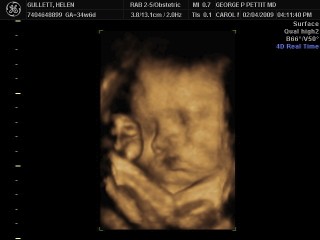

Kali ini adalah USG yang keempat yang dilakukan untuk memonitor perkembangan dan pertumbuhan bayi kami dalam kandungan saya. Kali ini semua organ dan anggota tubuh sudah berkembang dan sempurna. Dan dia juga adalah bayi yang “besar” karena kali ini beratnya sudah mencapai 3,2 kg (7 pon). Menurut dokter, itu adalah berat bayi yang sudah berusia 38 minggu padahal dia masih berusia 35 minggu. Sungguh bersyukur dan puji Tuhan walaupun dia adalah bayi yang besar, dia tetap sehat dan tidak ada kelainan karena dia berukuran besar. Kali ini saya sudah sekitar 65 kg. Itu berarti saya sudah naik 17 kg. Dokter juga mengatakan dia akan melakukan sekali lagi USG untuk melihat pertumbuhan bayi kami tanggal 25 Februari nanti. Dia akan melihat seberapa besar perkembangan ukurannya dan akan menentukan bagaimana cara saya melahirkan nanti, apakah itu secara normal atau terpaksa harus di operasi.